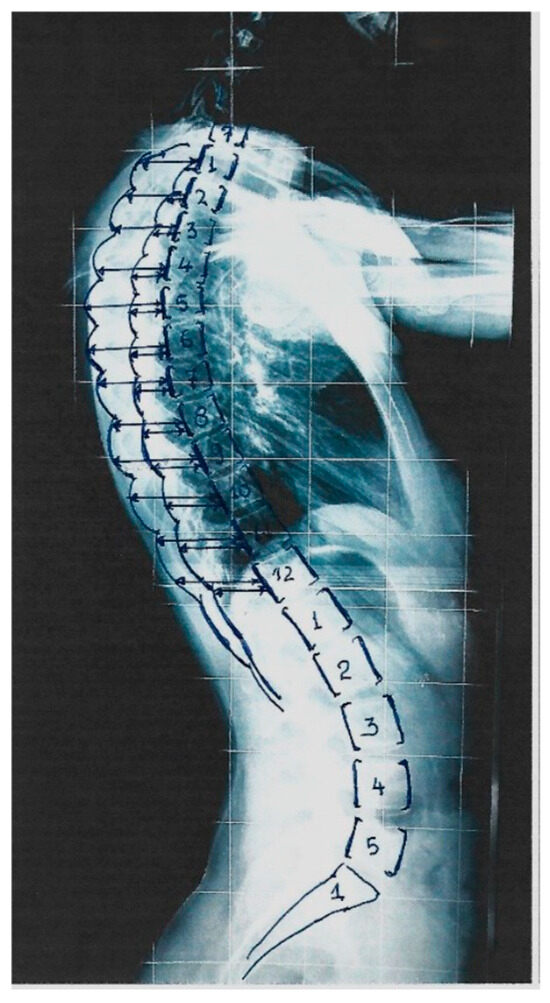

5. Segmental RI for Spinal Deformity

Originally, the RI was assessed at a selected thoracic level where the DRCS was at its maximum asymmetry. It was noticed that in the mild and moderate IS lateral spinal standing radiographs, the level of maximum asymmetry of the DRCS varied on a vertebral level in the different types of IS. This observation triggered us to assess the RI segmentally at all thoracic vertebral levels (T1–T12) and to evaluate the association of the Cobb angles of the various IS curves with the thoracic level of the RHD. A segmental RI (SRI) study of the ribcage from T1 to T12 was then implemented and published [12], as shown in Figure 3. This study included children and adolescents who were suffering from mild to moderate IS and additional asymmetric pairs in the thorax, but not scoliotic. The measurements included scoliometric readings of the angle of trunk rotation (ATR) for truncal asymmetry (TA), the Cobb angle assessment and the SRI from T1 to T12. The SRIs of the mild and moderate thoracic, thoracolumbar and lumbar curves were then presented for the first time. An SRI value of ≥1.45–1.50 was characterized as significant, namely signifying remarkable rib asymmetry and probably prognosticating the curve progression.

Figure 3.

The Segmental Rib Index (SRI) of the thoracic cage in a standing spinal radiograph (from our citation no. [16]).

In females with thoracic curves, a pattern of SRI asymmetry was present from T3 to T10 (RI = 1.59–1.75); in the thoracolumbar curves, there was a pattern from T2 to T5 (RI = 1.46–1.67), while in the lumbar curves, the RI did not exceed a value of 1.45 at all levels. In thoracic scoliotic girls, not only was the statistical significance of the correlation of the SRI with the ATR stronger, but also in more vertebral levels (T6–T12). For the thoracolumbar and lumbar curves, this correlation was not significant at any level. This implies the leading role of the rib cage, especially for the development of thoracic spinal deformity in girls.

In males with thoracic curves, the pattern of SRI asymmetry was from T6 to T11 (RI = 1.51–1.75), i.e., in lower levels compared with the female pattern of the RI in the thoracic curves. For the thoracolumbar curves, the pattern of SRI asymmetry was from T3 to T5 (1.50–1.52) and T7 to T12 (1.58–1.70), i.e., in a much lower and more extended number of rib-pair levels compared with the RI pattern of the females. This was a novel finding, indicating that the boys’ thoracolumbar curves were linked to caudal (lower thoracic levels) RC asymmetry, while in the girls’ thoracic curves, a more cephalad RC asymmetry is observed. In the boys with lumbar curves, the RI did not exceed a value of 1.44.

Additionally, the SRIs and Cobb angle correlations in the females showed significant differences between the thoracic, thoracolumbar and lumbar curve groups at the T8, T9 and T12 vertebral levels, whereas the post hoc analysis (multiple comparison tests) showed a significant difference between the thoracic and lumbar groups at t8, a significant difference between the thoracic and thoracolumbar groups at T9 and a significant difference between the thoracolumbar and lumbar groups at T12. The same analysis in the IS males only showed no significant difference between the groups. The findings of this research emphasize the importance of the role of ribcage asymmetry in relation to spinal deformity, mainly in girls [12].